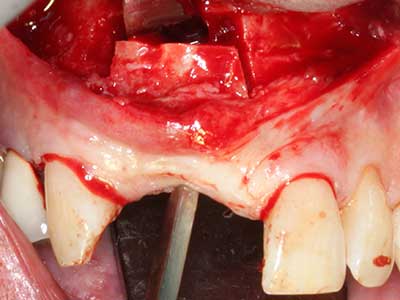

Piezo surgery has additional advantages when harvesting bone blocks. In addition to the high precision with osteotomy described above, the use of the thin saw tips specifically minimizes loss of material. Greater loss of material during harvesting can be expected with the thicker instrument tips, particularly when using Lindemann drills (Lakshmiganthan, Gokulanathan et al. 2012). The basal separation, which is necessary particularly for retromolar block transplants, is simplified by specially designed rectangular saws, with the result that piezo surgery is viewed as a precise, simple and safe procedure for harvesting retromolar bone blocks (Happe 2007) (Fig. 1-12).

Fig. 2: Vertical and horizontal lateral maxillary defect with a high smile line with indication for pre-implant reconstruction.

Fig. 5: Checking the block size at the recipient site.